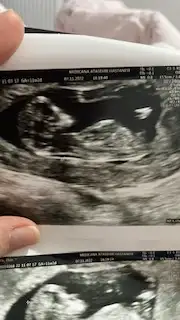

Cnm erkek gibi geldi bana hayirli gelsinTahmin yapabilen var mi

Kız gibi dedi sadece doktor ama kesin konuşmadı.erkek gibi. ultrasonda göremediniz mi? benim 12+3te ultrasonda belliydi cinsiyeti.

bacakları kapatmış o yüzden belli olmuyor. belki ultrason anında göstermiş olabilir.Tahmin yapabilen var mi

Kıza benzettibacakları kapatmış o yüzden belli olmuyor. belki ultrason anında göstermiş olabilir.

Cnm kız gibi duruyor12+ 1 haftalik

Cano bu erkek gibi şekli var ama tabi ilerde daha net bir şekilde yorumlanır nub teorisinden